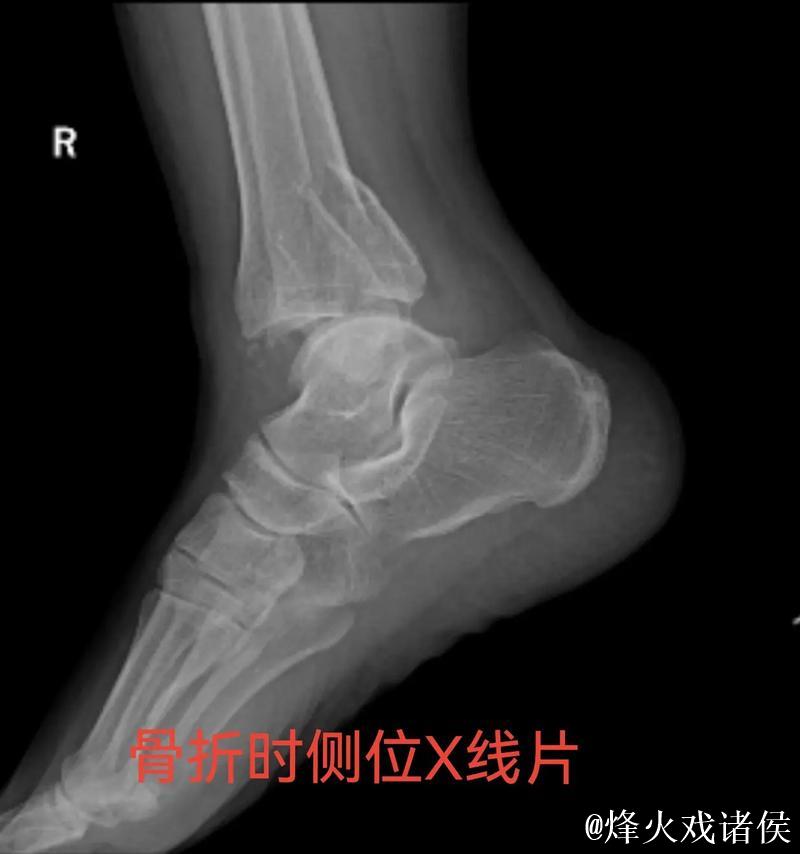

伤情解析 右踝三角韧带与腓骨骨折意味着什么

很多人在看到“右踝三角韧带断裂 右侧腓骨骨折”这样的医学表述时,只会感觉到“很严重”三个字,却未必真正理解其中的含义。踝关节三角韧带位于脚踝内侧,是一个由多条韧带组成的“组合体”,主要负责保持踝关节的内外稳定,防止小腿和足部出现异常翻转。当运动员在高速突破、急停、变向或落地时,如果脚踝遭遇过度外翻或扭转,三角韧带就可能被强行拉伸甚至撕裂。完全断裂不仅会造成剧烈疼痛,还会直接破坏踝关节的稳定性,使人几乎无法正常负重行走。与之同时出现的右侧腓骨骨折,大多与剧烈外力撞击或扭转应力有关。腓骨虽然不像胫骨那样承担大部分体重,但在踝关节的力学链条中起到重要支撑和协同作用。当韧带与骨骼在一次意外中同时受损,就意味着踝关节遭遇了极端应力,恢复与康复的难度成倍增加。